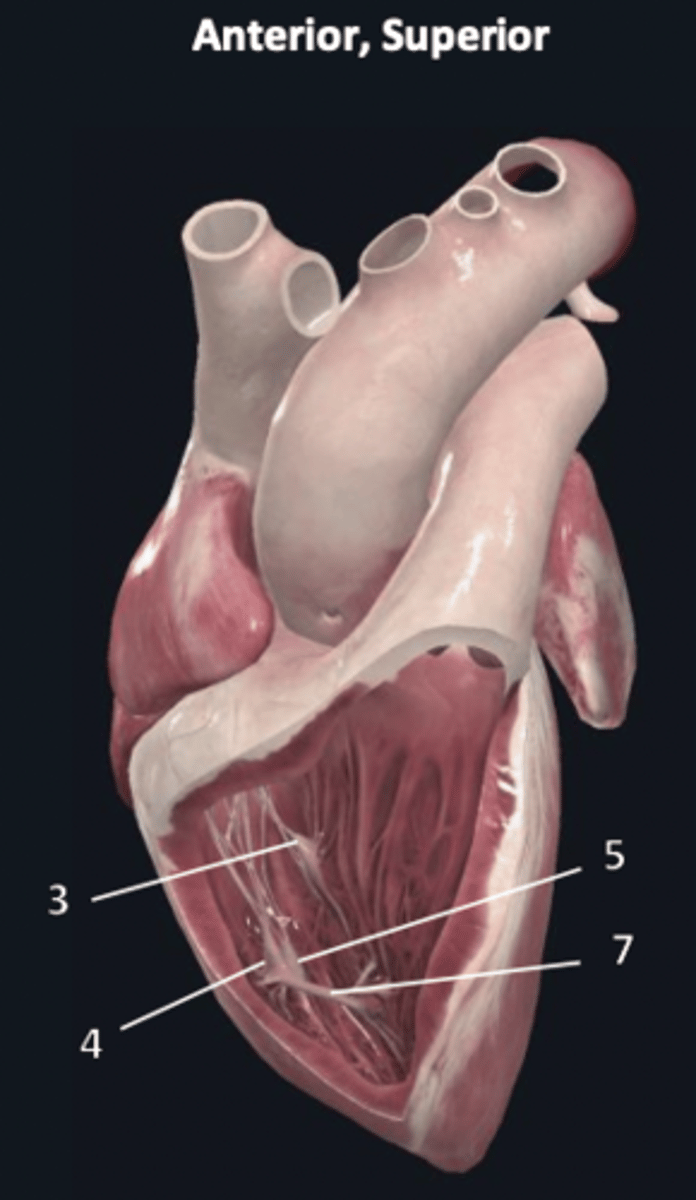

septal papillary muscle

3

anterior papillary muscle

4

inferior papillary muscle

5

chordae tendineae

6

moderator band

7

tricuspid valve

8

pulmonary semilunar valve

9

interventricular septum

10